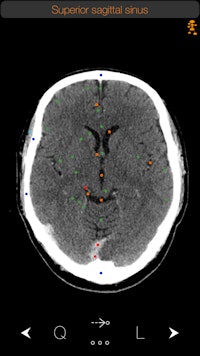

Winner: CT Anatomy (iOS), iCat Medical Software

The winner of this year's award for Best Mobile App is CT Anatomy, which was developed by George Michalopoulos, the CEO and founder of iCat Medical Software.

Originally a radiographer at a hospital in the U.K., Michalopoulos was frustrated by the lack of real-world apps that displayed human anatomy. Apps based on medical illustrations were available, "but you never see illustrations in real life in CT," he told AuntMinnie.com.

So in 2009 Michalopoulos began developing an app as a side project, releasing iRad CT in 2010. Inspired by the response to the software, Michalopoulos continued working at his hobby, releasing CT Anatomy in 2012.

The side project has now turned into a business. Michalopoulos currently employs five people who work full time on medical apps, with a number of part-timers also helping out. The company has a stable of 10 medical apps, with CT Anatomy remaining its flagship product.

CT Anatomy educates users on the appearance of normal human anatomy as seen on CT. The images are based on actual human scans that are scrubbed of identifying information.

iCat has recorded more than 15,000 downloads of CT Anatomy from the iTunes App Store. The software is available as a standalone offering for $9.99 or as part of a bundle with two other apps: X-Ray Anatomy and a radiography positioning atlas.

CT Anatomy is currently on version 6, but iCat hopes to make version 7 available this month. The new iteration includes better navigation with one-finger scrolling, easier navigation between the mediastinum and lung windows, and various bug fixes. What's more, iCat has doubled the number of chest images available, shifting from 25 to 50.